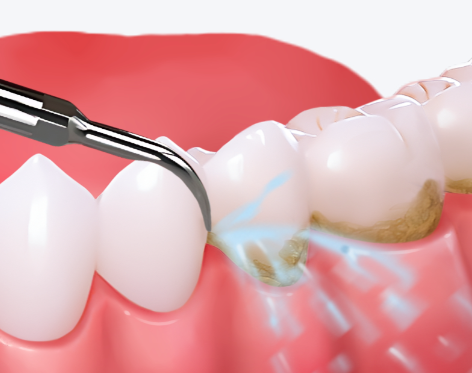

西安雁塔天瑞口腔门诊部成立于2013年,是一家经西安市市场监管部门批准的正规私立口腔医疗机构。门诊部提供活动义齿、种植牙、口腔修复、洗牙、拔牙、牙周治疗、牙齿美白、补牙等多项诊疗项目。其特色在于汇聚了西安交大及第四军 医 大的有医生师,能为客户提供高端的口腔医疗服务。诊疗环境舒适宜人,配备现代化的诊疗设施和精良的医疗设备。门诊部人员规模少于50人,参保人数20人。虽然暂未提及荣誉成就,但凭借其专精的医生团队和优质的服务,在患者中拥有良好的口碑,深受大家的信赖。

1. 活动义齿:能根据患者的口腔情况,定制个性化的活动义齿,修复咀嚼功能的同时,提升美观度。

2. 种植牙:采用精良的种植技术,由经验多的医生操作,确保种植成效稳定、持久。

3. 口腔修复:针对牙齿缺损、缺失等问题,提供专精的修复方案,使牙齿修复正常功能和外观。